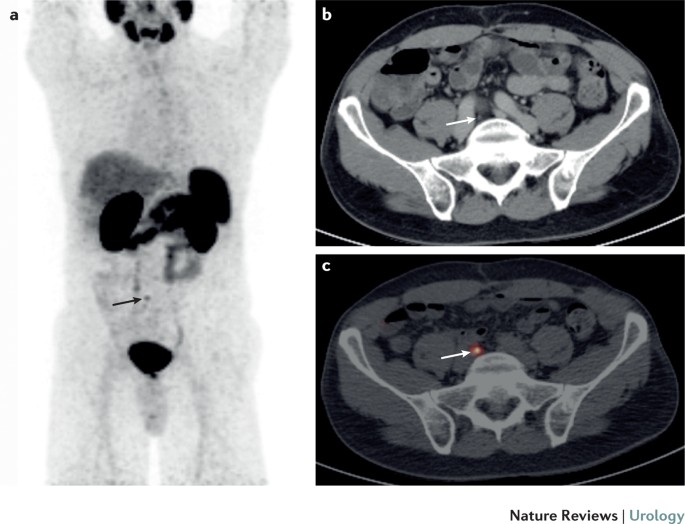

Psma Pet Ct In Initial Prostate Cancer Staging Nature Reviews Urology

Scielo Brasil Impact Of Sup 68 Sup Ga Psma Pet Ct On Treatment Of Patients With Recurrent Metastatic High Risk Prostate Cancer A Multicenter Study Impact Of Sup 68 Sup Ga Psma Pet Ct

68 Ga Psma Pet Ct Identified Solitary L5 Metastasis In Patient With Download Scientific Diagram